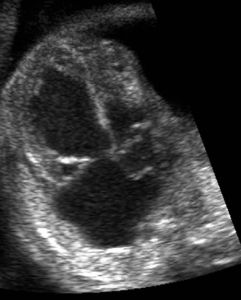

Fetal Echocardiography

WE ROUTINELY DO FETAL ECHOCARDIGRAPHY AT OUR CENTRE